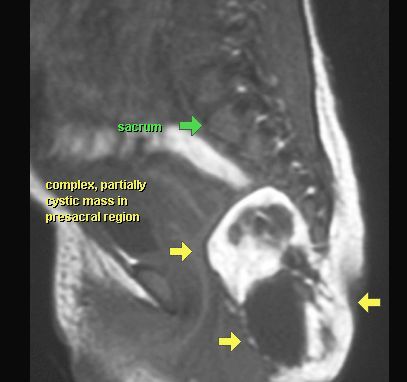

POTWORNIAK

MR